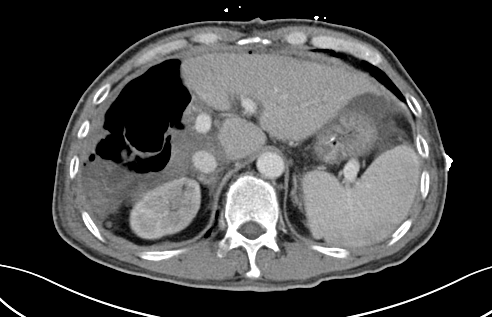

二次手術(shù)完整切除腫瘤

于是,專家團(tuán)隊便于10月中旬為患者實施了第二階段腫瘤切除術(shù),在此過程中,由于患者同時合并腹繭癥,通過第一次手術(shù)的刺激腹腔內(nèi)粘連非常嚴(yán)重,手術(shù)遭遇了巨大的困難,最后經(jīng)過近7小時左右的艱苦奮戰(zhàn),攻堅克難,終于完整切除了患者右肝的巨大腫瘤,手術(shù)取得了成功,患者重獲新生。

術(shù)后,患者經(jīng)過10多天的恢復(fù)治療,順利康復(fù)出院。出院后,經(jīng)科室多次電話回訪,現(xiàn)患者身體狀況和生活質(zhì)量良好。